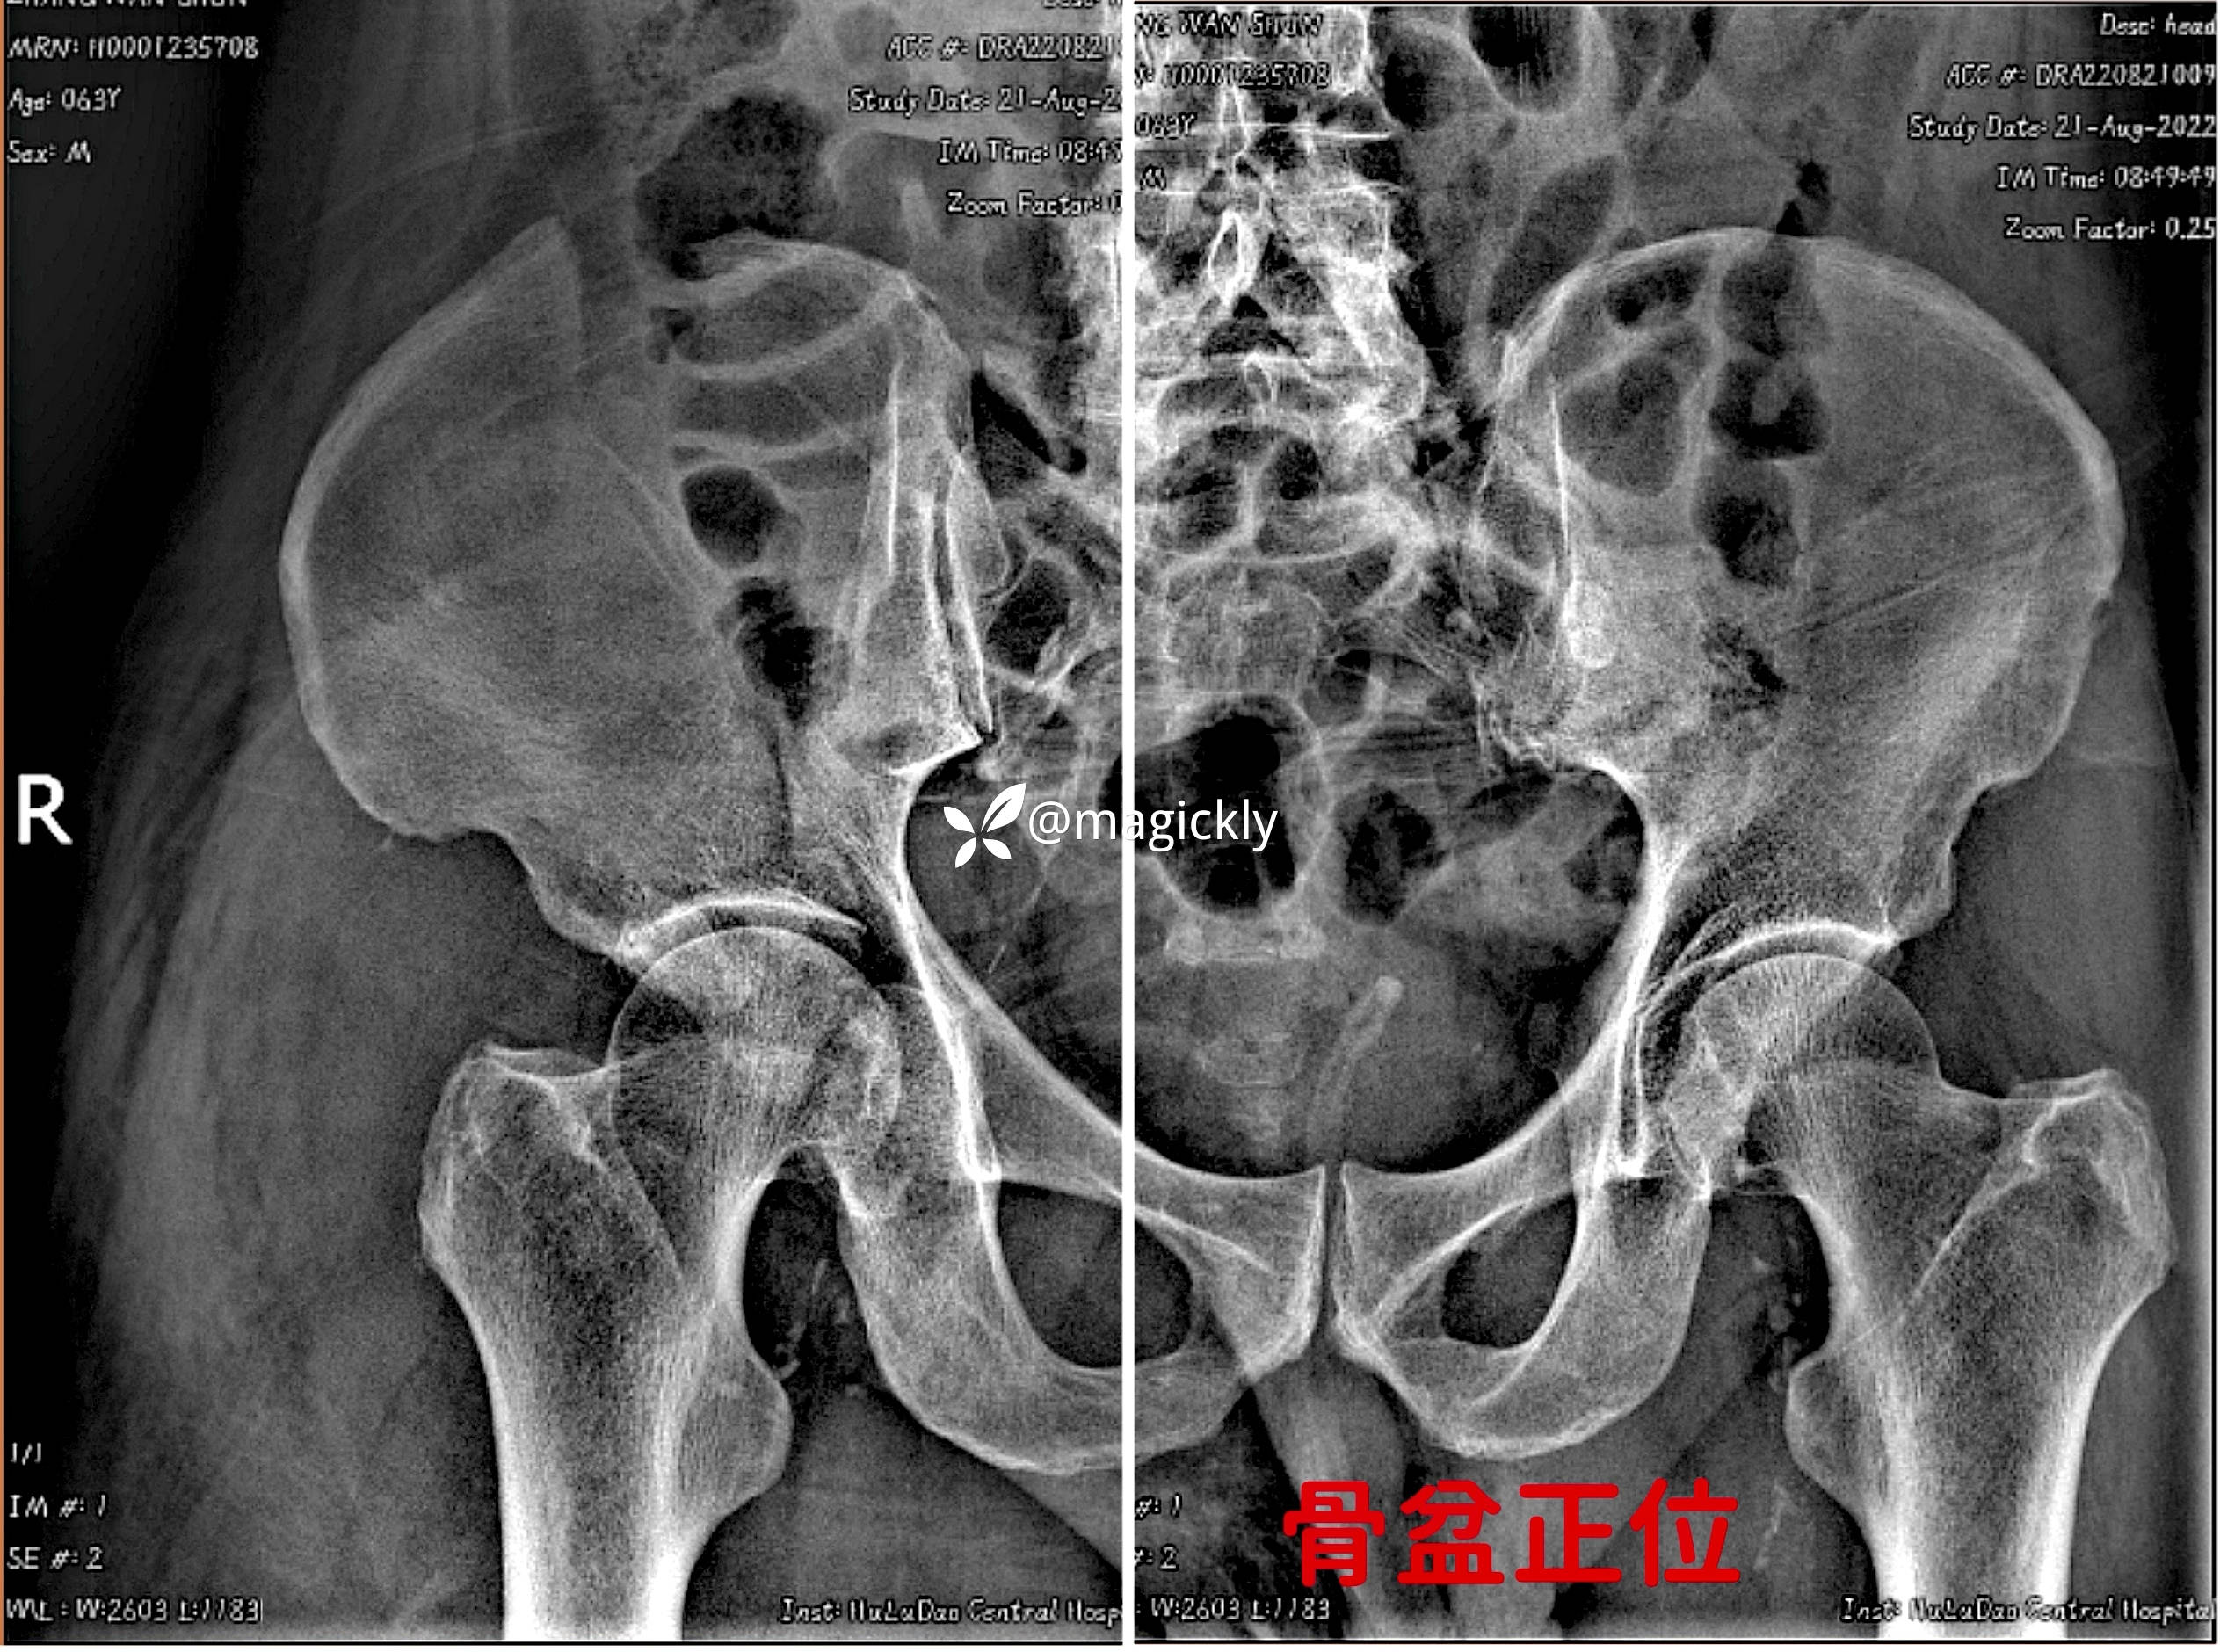

【检查】:局部体征明确,影像学结果如下

【临床诊断】:髋臼骨折(后上壁)